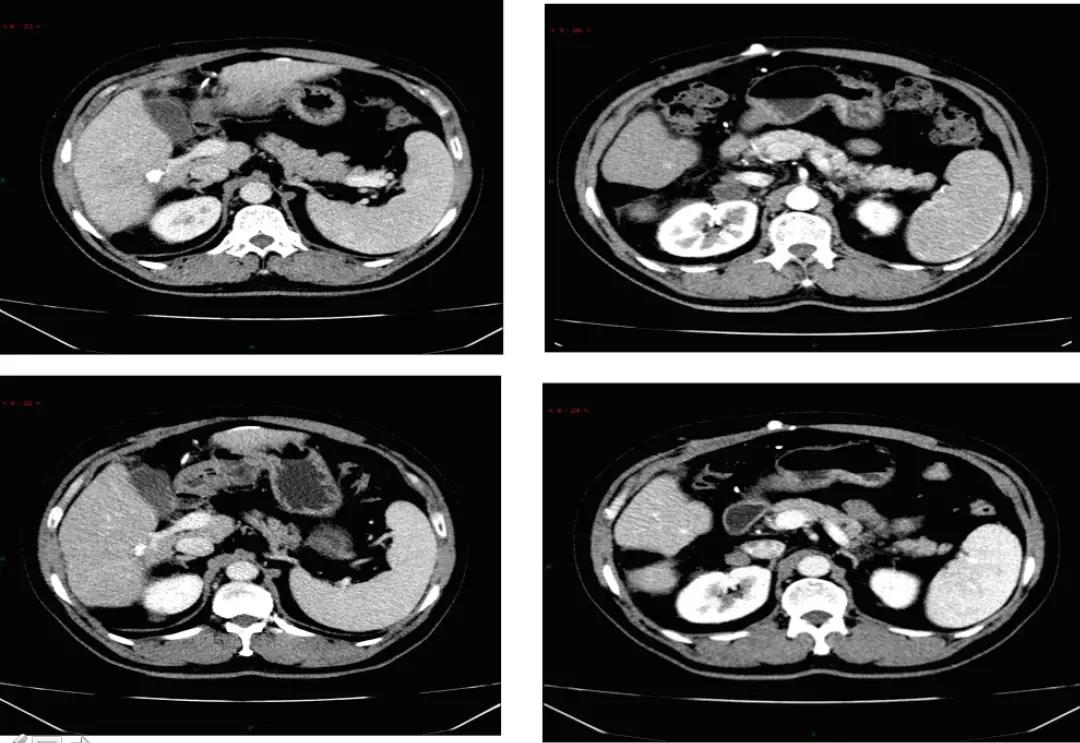

2019年9月21日患者出现乏力,纳差加重,体力下降。复查CT发现肝内病灶稳定,但右侧腹膜后淋巴结增大。疗效评价:疾病进展(PD;图2)。ECOG评分:1分。肝功能良好。2019年9月24日更换为口服瑞戈非尼片160mg QD,服3周停1周,4周为1周期。不良反应包括:胃肠道刺激,恶心,纳差,偶有呕吐,肌肉疼痛,乏力,皮肤粘膜反应,高血压轻到中度,给予硝苯地平缓释片控制血压,吗丁啉促进胃动力,奥美拉唑口服保护胃黏膜,间断使用芬必得控制肌肉疼痛等对症处理措施。耐受不好时偶有自行减量为120mg,但非连续发生。2019年11月19日,复查肝内病灶稳定,腹膜后淋巴结稳定。2020年2月5日,复查肝病灶稳定,腹膜后淋巴结缩小,疗效评价为部分缓解(PR;图3)。